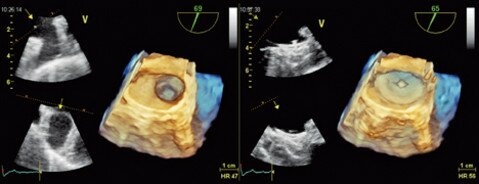

Die Abbildung unten zeigt das Vorhofohrverschlusssystem der Firma St. Jude Medical, was aus zwei Teilen besteht: Einem Körper, der das Gerät im Vorhofohr verankert und einem Deckel, der das Vorhofohr von oben zusätzlich versiegelt. In einem dreidimensionalen Herzultraschall können Sie die Funktion des Deckels besonders gut erkennen.